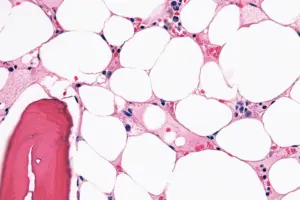

Average Costs Of Tumescent Liposuction

A common technique where a tumescent solution of saline, lidocaine, and epinephrine is injected into fatty tissue to swell it, facilitating precise fat removal while minimizing pain, bleeding, and bruising.